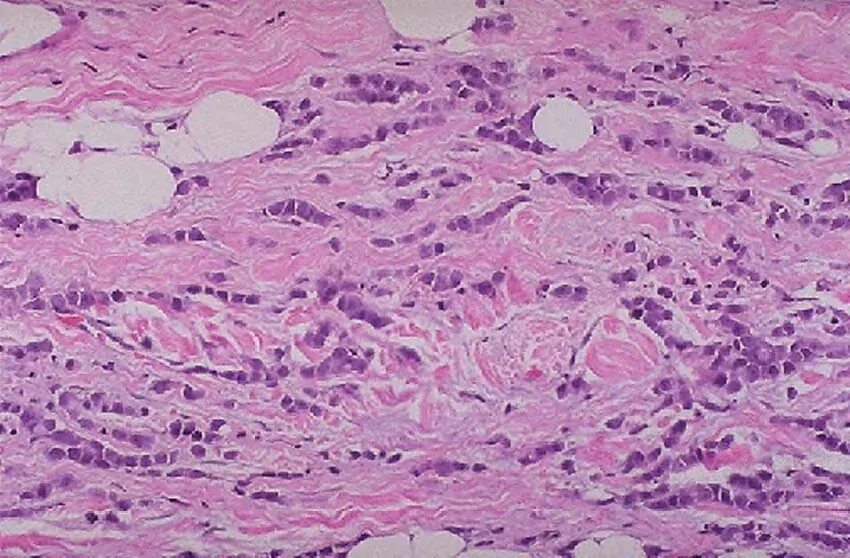

Гистология фиброзные фрагменты